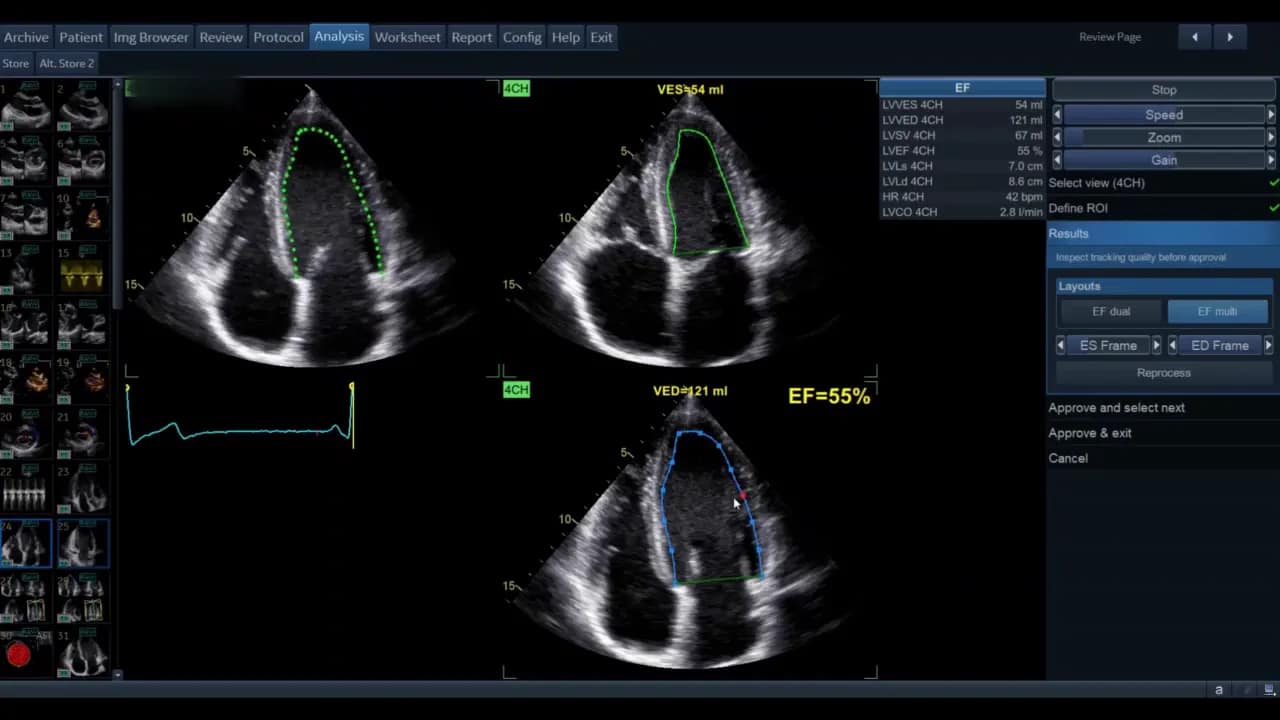

Schritt 4: Prozessierung und Erkennung von Enddyastole/Endsystole

Klicken Sie auf Process, um die automatische Verfolgung starten zu lassen. Die Software identifiziert dann den Enddiastolen‑ und Endsystolen‑Frame.

Enddiastole bezeichnet den Zeitpunkt maximaler Volumenfüllung des LV. Endsystole ist der Zeitpunkt minimalen LV‑Volumens. Diese Frames sind die Basis für die Volumenberechnung mittels Simpson‑Methode der Scheiben.

Die Ansicht kann als Einzelbild oder als EF‑Dual‑Display gezeigt werden. Im Dual‑Display sehen Sie gleichzeitig Systole und Diastole mit den berechneten Volumina und der Ejektionsfraktion als Prozentsatz.

Für die standardisierte Ejektionsfraktionsbestimmung wird häufig die modifizierte biplane Simpson‑Methode verwendet. Dazu müssen die Werte aus APL4 und APL2 kombiniert werden. Nach Freigabe der Vierkammer‑Ansicht wählen Sie Approve und Next. Die View‑Recognition sollte automatisch die passende Zweikammer‑Ansicht anzeigen.

Die Software zeigt nach erfolgreichem Durchlauf die systolischen und diastolischen Volumina beider Ansichten sowie die berechnete biplane Ejektionsfraktion. Diese Werte erscheinen in der Ergebnisliste; die biplane EF wird in der Regel als kombinierter Wert ausgewiesen.

Interpretation der Ergebnisse

Die AutoEF liefert Volumina für EDV (end‑diastolic volume) und ESV (end‑systolic volume) sowie die EF. Interpretieren Sie die Werte im klinischen Zusammenhang:

- Leicht reduzierte EF (40–49%) kann auf beginnende systolische Dysfunktion hinweisen.

- Moderat bis stark reduziert (< 40%) erfordert weiterführende Diagnostik und Therapieüberlegungen.